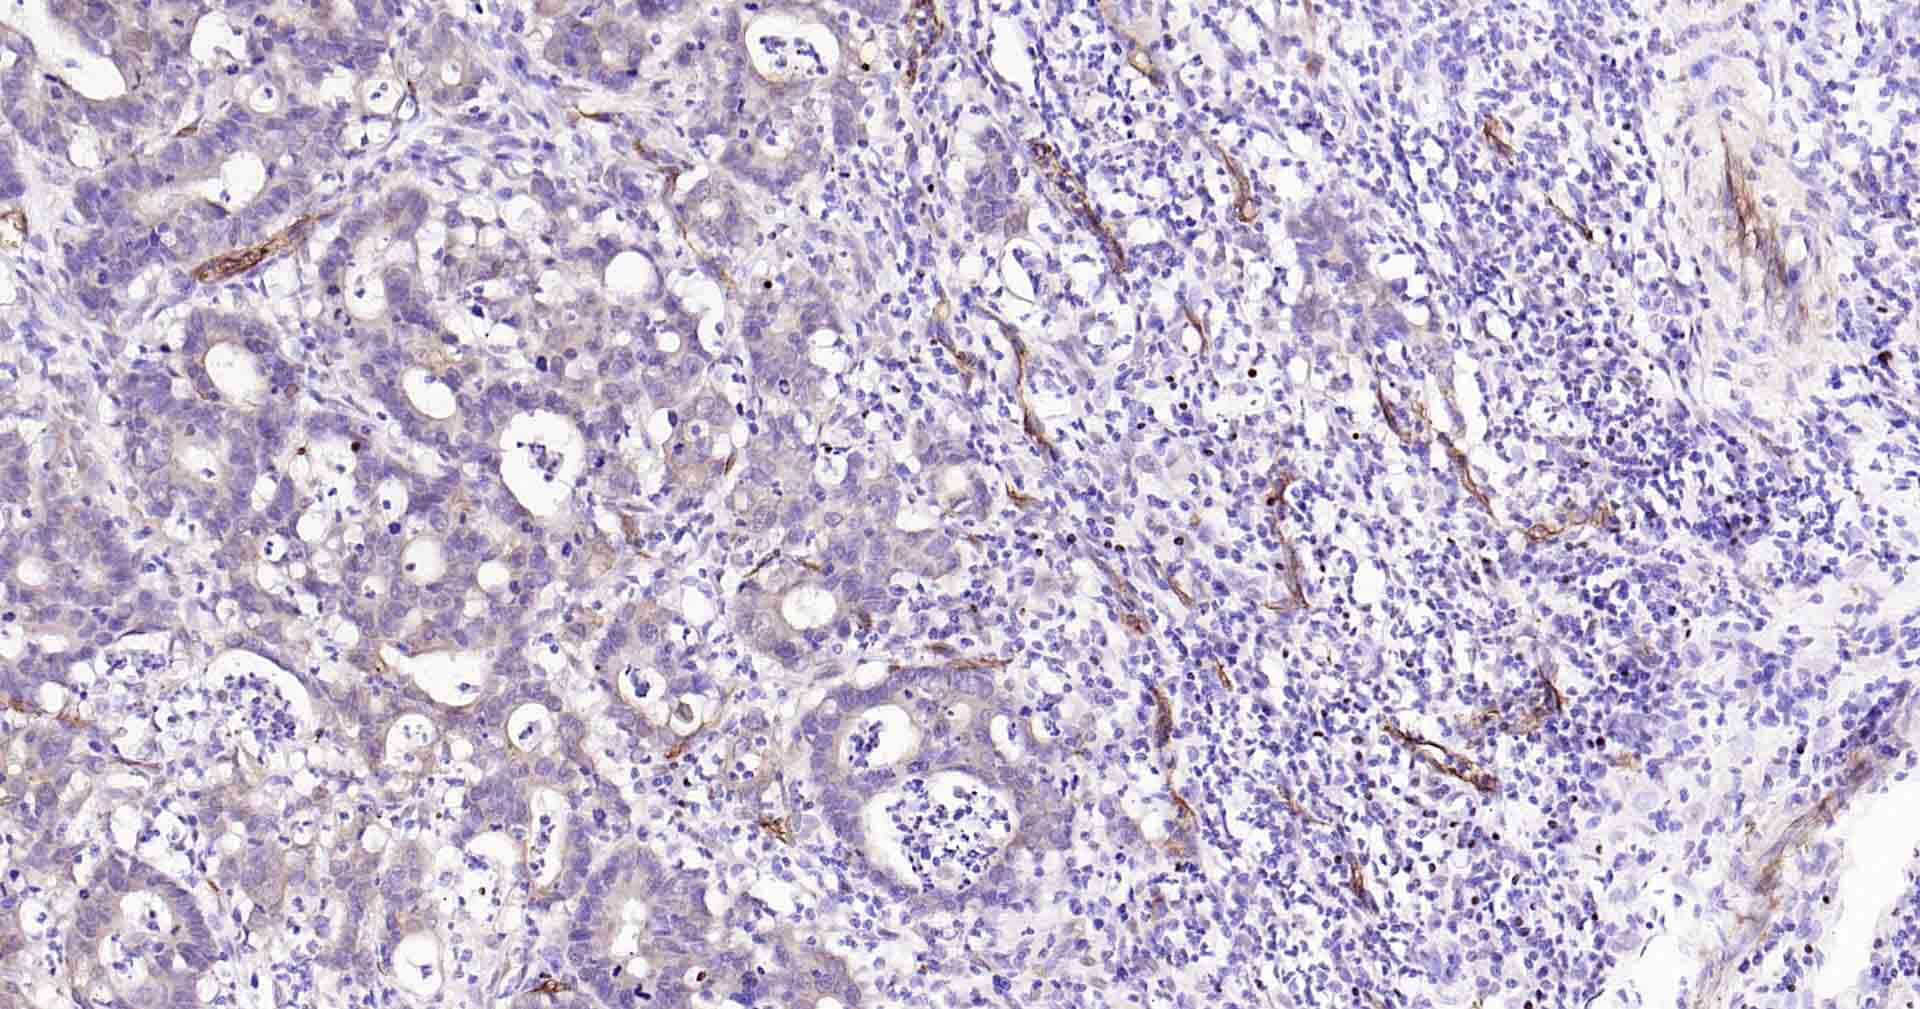

Paraformaldehyde-fixed, paraffin embedded Human Breast ; Antigen retrieval by boiling in sodium citrate buffer (pH6.0) for 15 min; Antibody incubation with AQP1 Monoclonal Antibody, Unconjugated(bsm-52909R) at 1:200 overnight at 4°C, followed by conjugation to the SP Kit(Rabbit, SP-0023) and DAB (C-0010) staining.